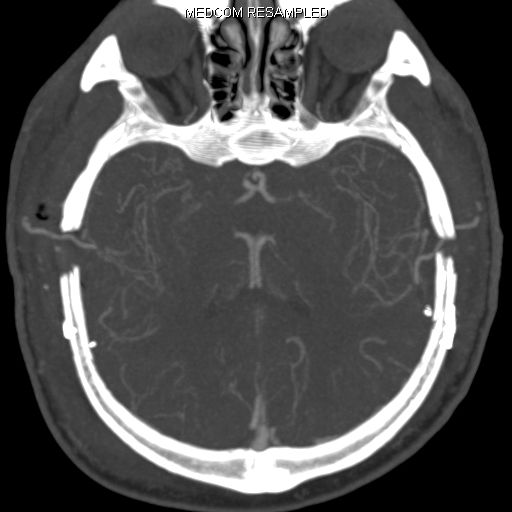

Die konventionelle cerebrale Angiographie ist die wichtigste Untersuchung zur Diagnosestellung der Moyamoya Krankheit. Diese Untersuchung ist zu vergleichen mit einer Herzkatheteruntersuchung, eben nur mit Darstellung der Hirnarterien. Bei Moyamoya-Patientinnen und Patienten werden, im Gegensatz zu Routineuntersuchungen bei anderen cerebralen Erkrankungen, selektiv die vordere und hintere Zirkulation des Gehirns dargestellt, sowie auch die Versorgung der extrakranialen Gefäße. Diese umfassende Darstellung ist besonders wichtig, um die vollständige Ausdehnung der Erkrankung zu erfassen und alle möglicherweise veränderten Blutflüsse im Gehirn zu verstehen. Je nach Befund werden die Engstellen der Hirnarterien, sowie auch mögliche begleitende Veränderungen selektiv hochauflösend dreidimensional dargestellt. Es ist wichtig zu erwähnen, dass die Moyamoya Krankheit nicht über eine Katheterintervention (Ballonaufweitung der Engstelle) behandelt werden kann und darf. Dies haben mehrere Studien gezeigt.

Angiographie beidseitige Moyamoya Krankheit

Konventionelle Angiographie eines Patienten mit beidseitiger Moyamoya Krankheit (links). 3-dimensionale Darstellung eines Aneurysmas einer jahrelang stark beanspruchten Spontan-Kollaterale (rechts).